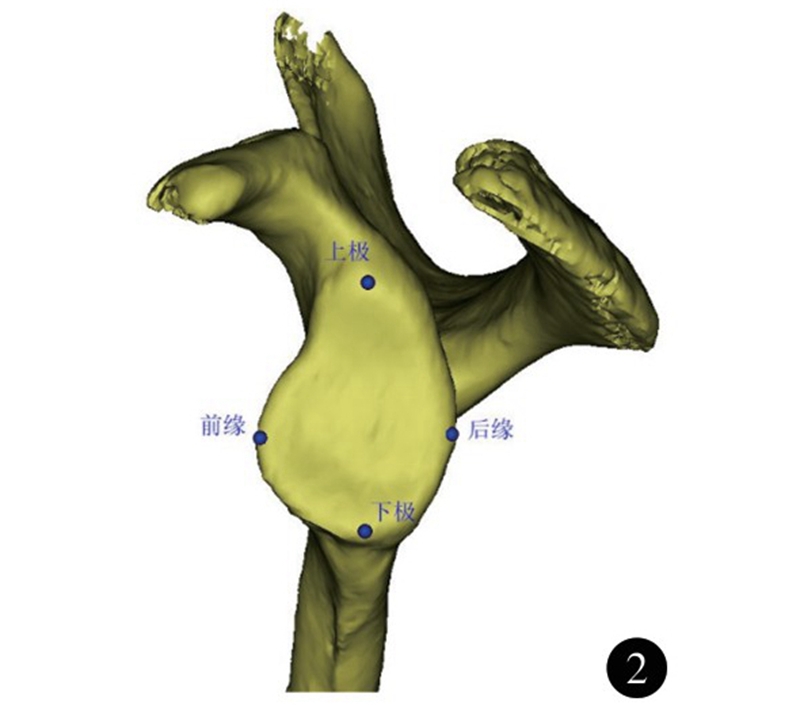

肩胛骨位于胸廓上方两侧偏后,紧贴胸后壁,与其构成类似关节的结构,称之为肩胛胸壁关节。肩关节活动时,肩胛骨沿胸壁活动,配合盂肱关节,完成肩关节上举,是肩关节的重要组成,并通过盂肱关节和肩锁关节将上肢连接于躯干上。 肩胛盂作为盂肱关节的组成部分,深度较浅,形态不规则,近似梨形;下半部分较上半部分大,比例约为1:0.8±0.1。众多研究测量了肩胛盂表面解剖学参数,其中肩胛盂上下径为肩胛盂最高点至最低的距离(图2) ; 其均值男女分别为33.6~37.5mm和29.4~33.8mm。肩胛盂前后径为位于与肩胛盂上下轴垂直平面的肩胛盂前后的最大距离;其均值分别为24.9~28.6mm和21.3~23.7mm。肩胛盂上下径、前后径存在显著的性别差异,男性肩胛盂较女性大10%左右。肩胛盂形态在性别上也有不同,男性肩胛盂下部较圆, 而女性为椭圆。Andrea等依据肩胛盂前缘切迹的形态将肩胛盂的形状分为 4 型(图3) : 0型(无切迹) 、Ⅰ型( 弧线型) 、Ⅱ型(切迹型) 、Ⅲ型(圆齿型) 。男女均以Ⅰ型(弧线型) 所占比例最高。肩胛盂前缘切迹在女性中出现的比例为80.4%;而男性中这一比例为 57.6% 。36.7%的女性切迹出现在顶部;而男性只有28.9%,两者差异有统计学意义。

图2 肩胛盂上下径、前后径示意图